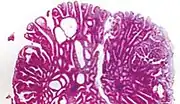

| Type | Risk of containing cancer cells | Histopathology | Image | |

|---|---|---|---|---|

| Hyperplastic polyp | 0% | No dysplasia.[13]

|

| |

| Tubular adenoma | 2% at 1.5cm[15] | Low to high grade dysplasia[16] | Over 75% of volume has tubular appearance.[17] |

| Tubulovillous adenoma | 20% to 25%[18] | 25%-75% villous[17] |

| Villous adenoma | 15%[19] to 40%[18] | Over 75% villous[17] |